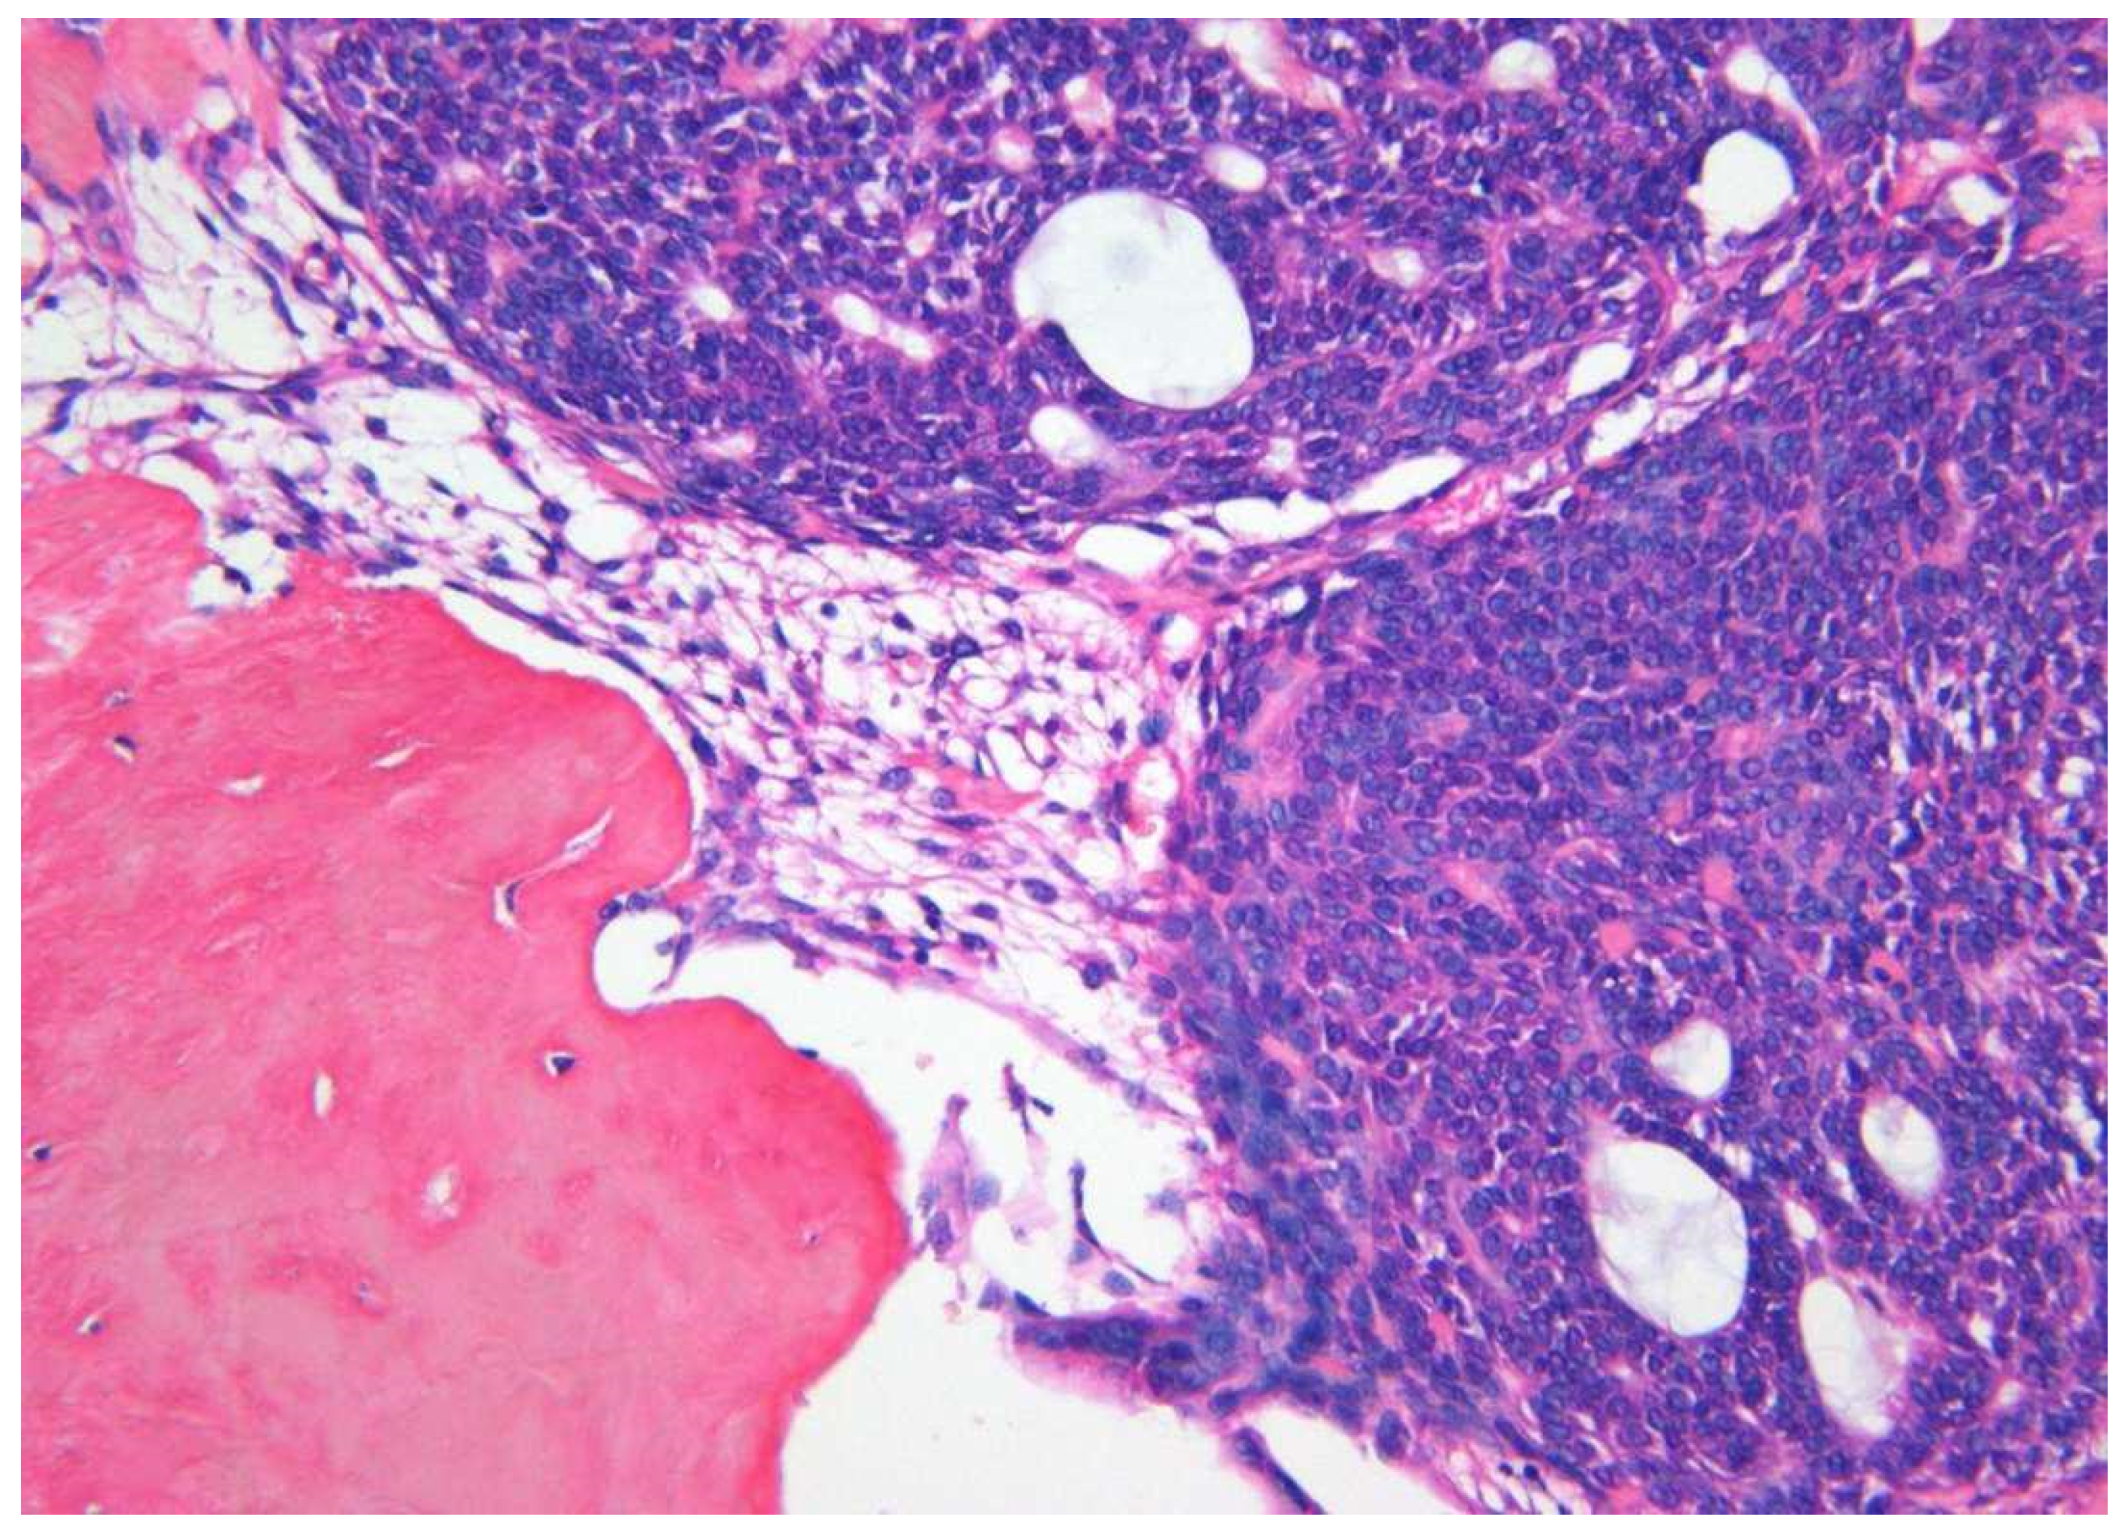

| Histopathology | ||||

| 1. Capsule-present | 10 (90.9) | 24 (80.0) | 34 | |

| 2. Epithelial component | ||||

| 2a. Duct like structures | 09 (81.8) | 27 (90.0) | 36 | |

| 2b. Epithelial whorls | 11 (100) | 29 (96.6) | 40 | p = 0.7 |

| 2c. Rosettes | 03 (27.2) | 19 (63.3) | 22 | |

| 2d. Trabeculae | 08 (72.8) | 25 (83.3) | 33 | |

| 3. Stromal component | ||||

| 3a. Tumour droplets | 08 (72.8) | 20 (66.6) | 28 | |

| 3b. Calcifications | 11 (100) | 29 (96.6) | 40 | p = 0.8 |

| 3c. Osteo-dentine | 01 (09.1) | 01 (03.3) | 02 | |